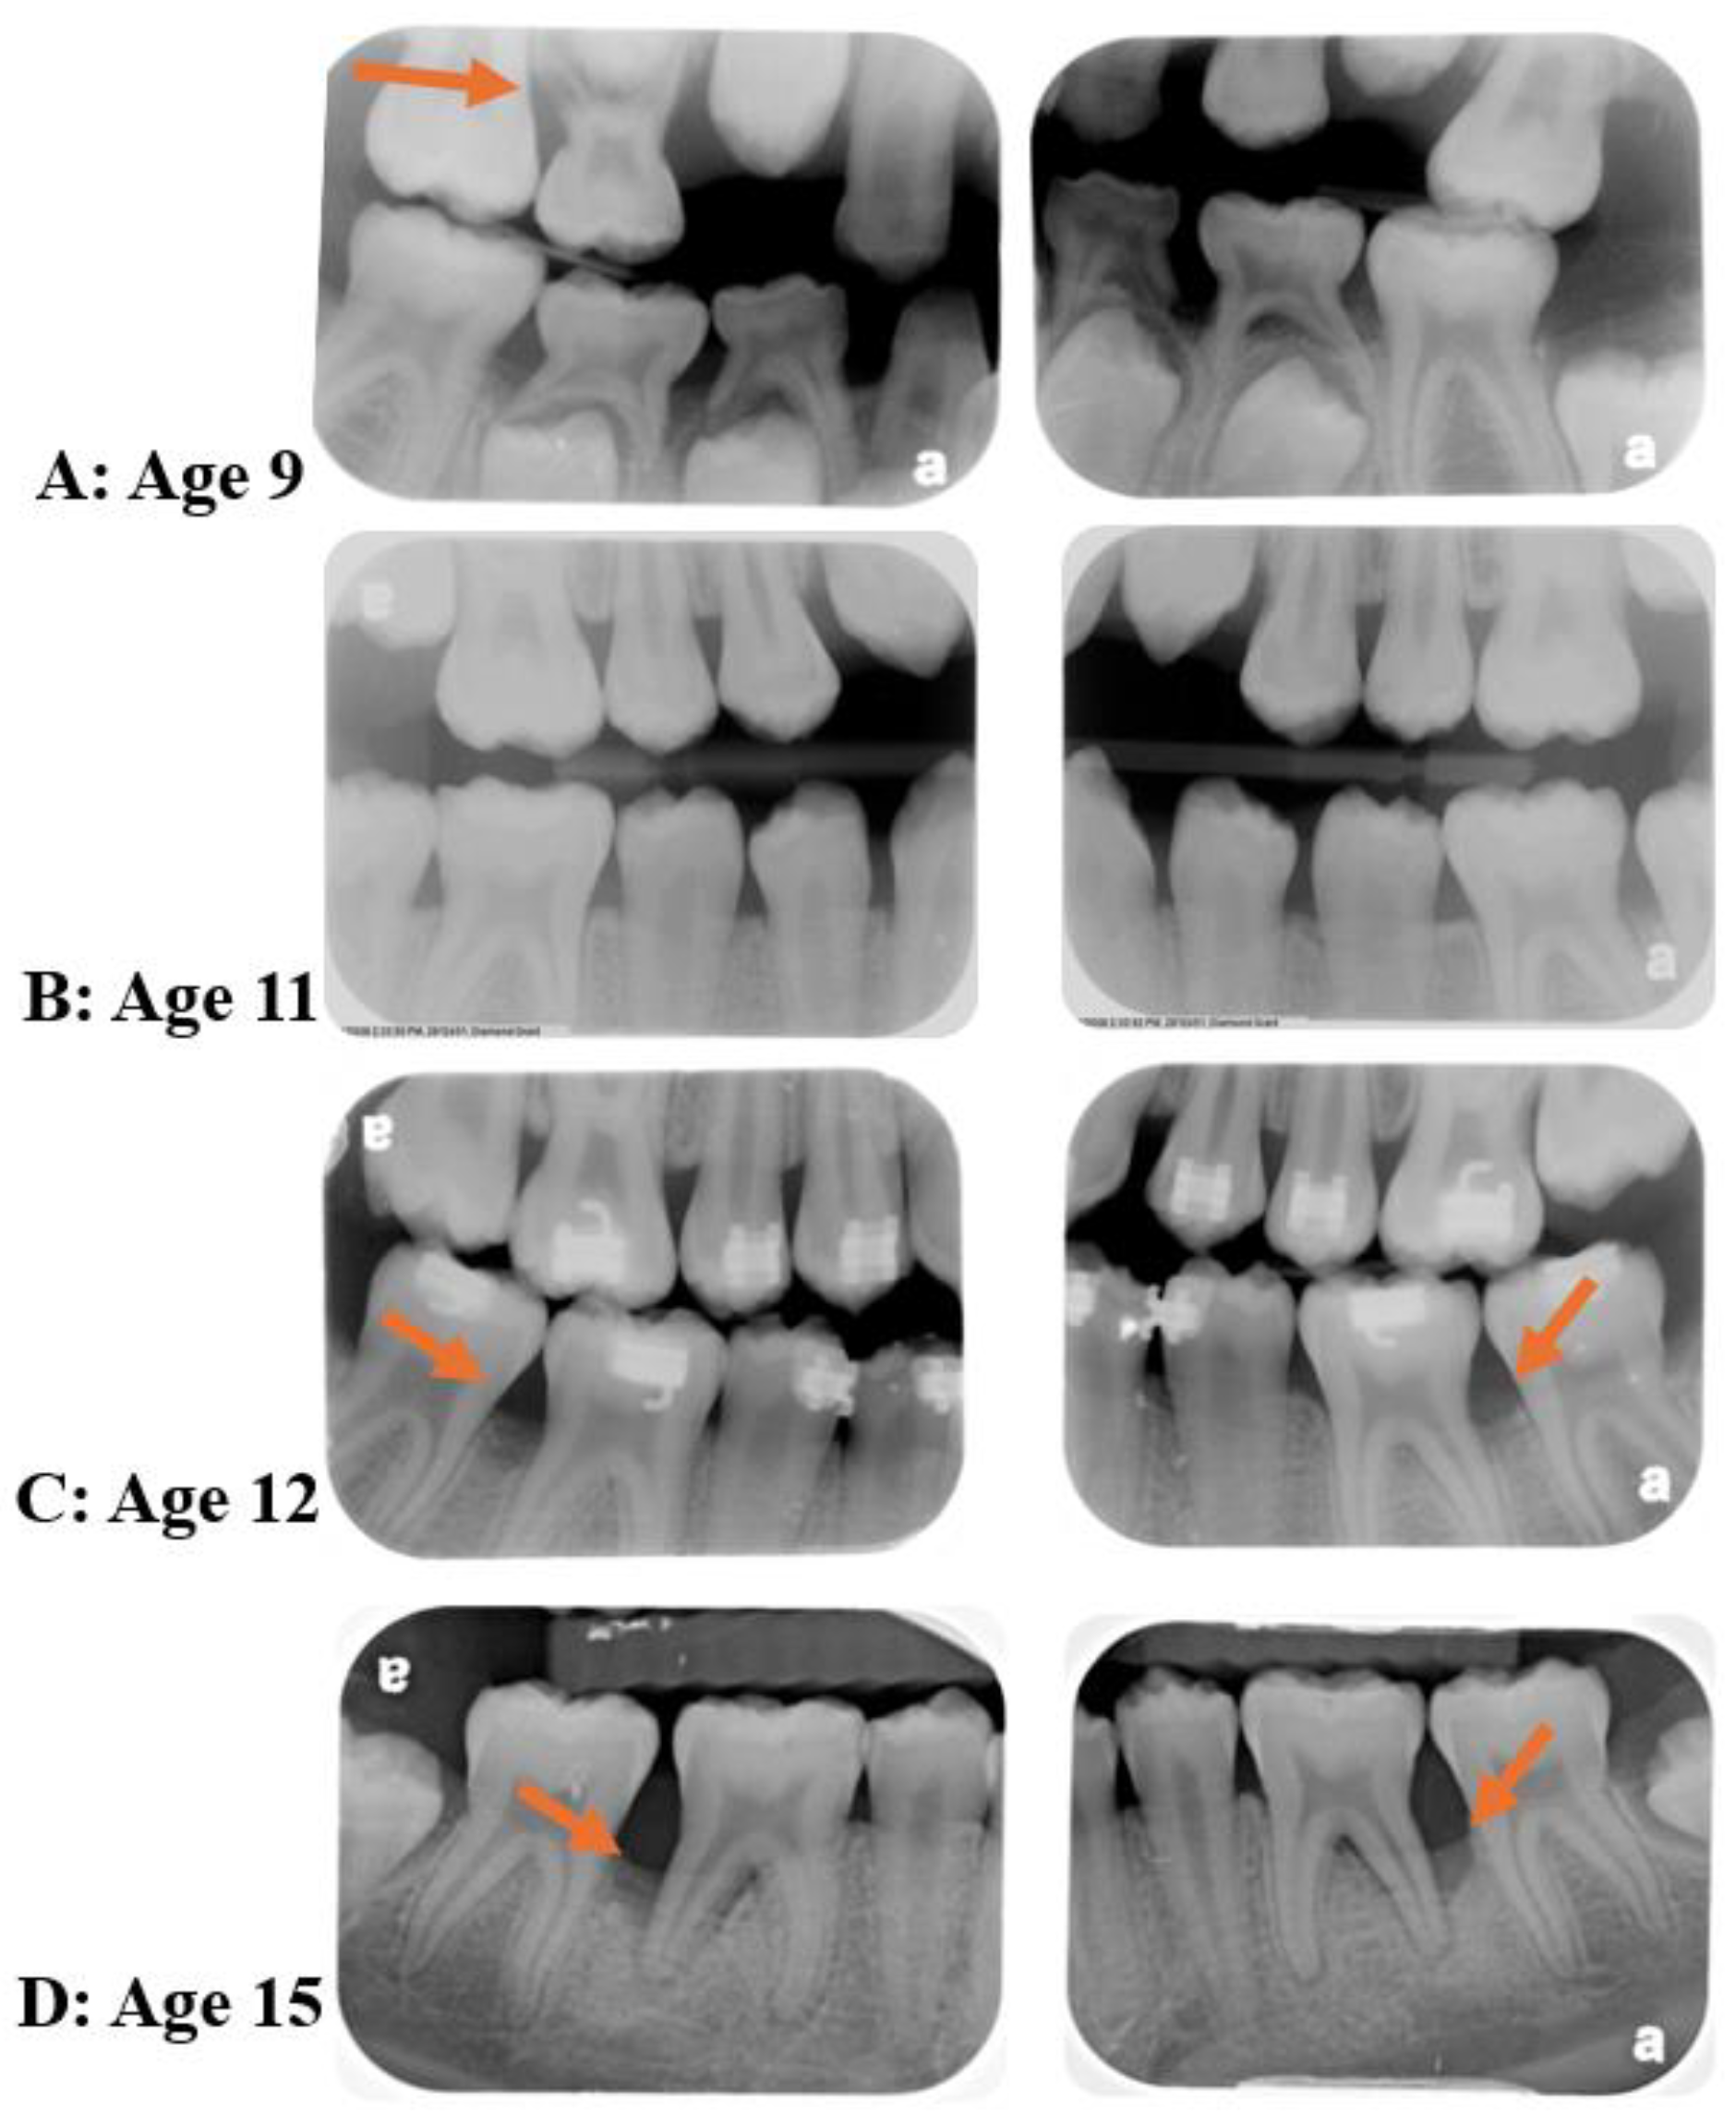

Figure 5.

Clinical Case: The patient was referred to periodontal treatment at age 15 with significant vertical bone loss on #19 and 30. Retrospective radiographic analyses of the permanent and primary dentitions show evidence of bone loss in the upper (orange arrow) and lower primary molars at age 9 (A), healthy permanent dentition at age 11 (B), and beginning of bone defects in permanent dentition at age 12 and 15 (C,D); #19 and 30 distal surfaces) (Source of the image [10]).